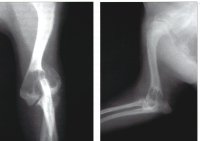

The

radiographs show marked osteolysis of the distal humeral metaphysis with

endosteal cortical lysis and absence of periosteal expansion. There is also a

Salter-Harris type IV fracture involving the lateral portion of the humeral

condyle with proximolateral displacement. The

differential diagnosis list should include :